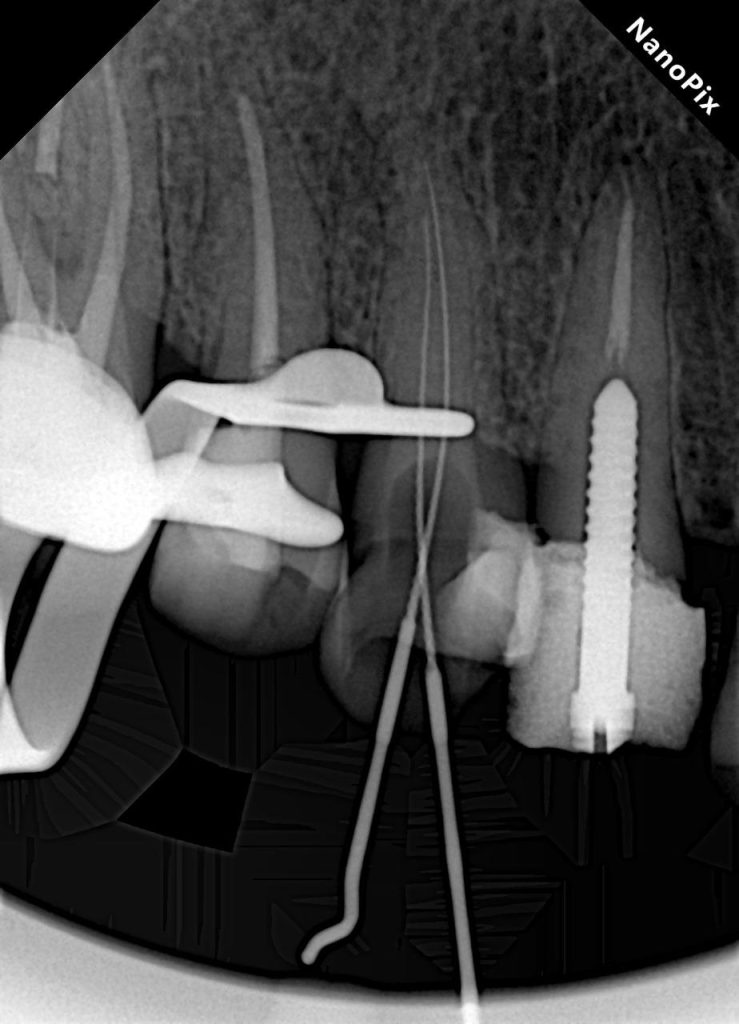

TREATMENT SEQUENCE

- Quadrant isolation and old restoration removal

- Endodontic retreatment (UL3 & UL6) and primary endodontic therapy (UL4–UL5–UL7)

- Deep Margin Elevation where required

- Post placement

- UL3: Cast Metal Post due to limited ferrule and previous metal post indication

- UL6: Fibre post to preserve biomechanical flexibility in a posterior functional tooth

- Core build-up using Dentsply SDR

- Tooth preparation for zirconia crowns

- Final cementation with dual-cure resin cement

ENDODONTIC TREATMENT PROTOCOL

- Isolation: Achieved using full quadrant rubber dam isolation

- Canal preparation: Rotary NiTi system

- Irrigation: NaOCl + EDTA final rinse

- Obturation: Single-cone technique using resin-based Kerr sealer

- Coronal seal: SDR composite immediately post-obturation

POST PLACEMENT

A ferrule assessment revealed compromised cervical strength in UL3 and UL6.

Both posts were adhesively luted to optimise retention and biomechanical reinforcement prior to core build-up.

CORE BUILD-UP & PREPARATION

All treated teeth were reinforced with SDR (Dentsply) as the base core material for its low polymerisation stress and strong dentine bonding compatibility. Tooth preparation was then carried out for monolithic zirconia crowns, maintaining conservative reduction to preserve tooth strength.